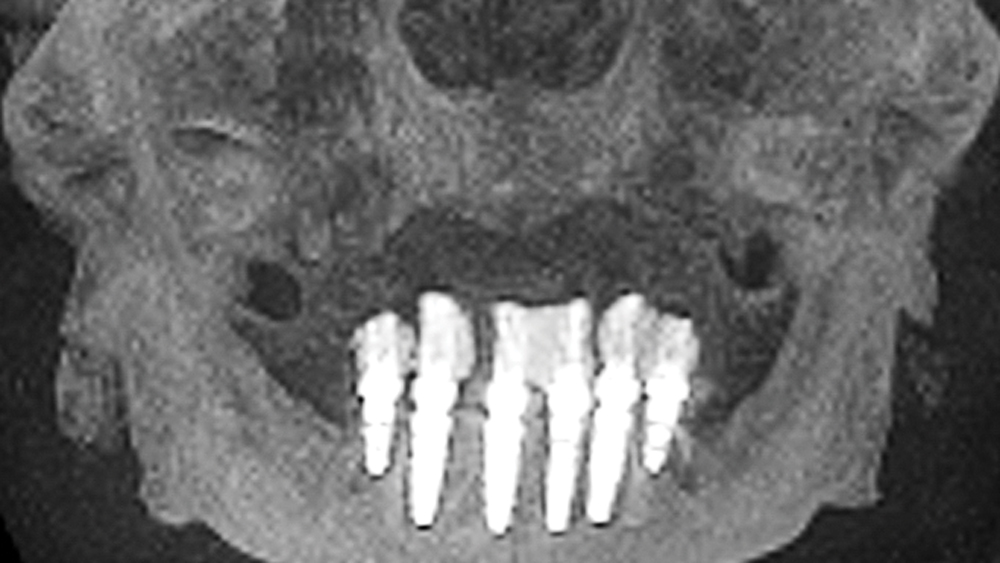

This patient was unhappy with the esthetics of her existing upper denture as well as the discomfort and instability caused by her loose-fitting mandibular partial denture. Although her concerns with the maxillary denture could be addressed with a new, more esthetic appliance, she preferred implant treatment for her mandible, where a fixed solution was needed to adequately restore function, stability and comfort.

Treatment plan:

The patient’s remaining mandibular teeth were extracted followed by immediate implant placement and delivery of a fixed provisional appliance. After integration of the implants, the prosthetic designs for the new upper denture and lower implant restoration were determined in tandem. Ultimately, the dual-arch restorations addressed the functional and esthetic challenges of the case while staying within the financial means of the patient, demonstrating the benefits of a flexible, multifaceted approach to restorative dentistry.